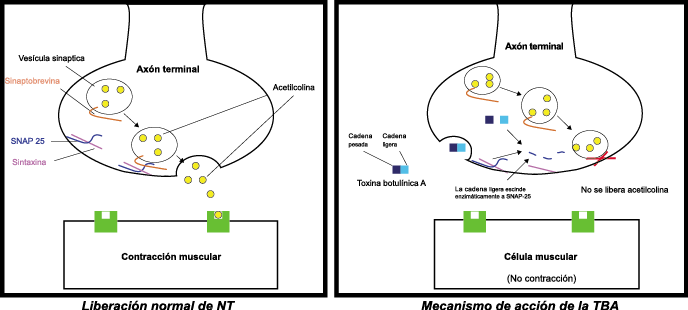

Toxina botulínica

La toxina botulínica tipo A (BT-A) fue descrita por primera vez por Binder y colaboradores en 1991 como tratamiento preventivo para la migraña al observar que cuando pretendían reducir líneas de expresión faciales en algunos pacientes estos vieron como también se redujeron los dolores de cabeza por migrañas. La BT-A ya ha sido utilizada previamente como tratamiento de otras afecciones tales como hiperhidrosis axilar, estrabismo, acalasia o alteraciones musculares como distonías y espasticidad. La inyección vía subcutánea de toxina botulínica tipo A (BT-A) en el cuero cabelludo, fue aprobada en 2011 por la FDA. Diversos estudios in vitro e in vivo han demostrado que la TBA inhibe la liberación de la sustancia P y de aminoácidos excitadores y péptido relacionado con el gen de la calcitonina) (Figura 29). Más recientemente, su efecto antinociceptivo ha sido relacionado con inhibición de liberación de glutamato (Figura 30).